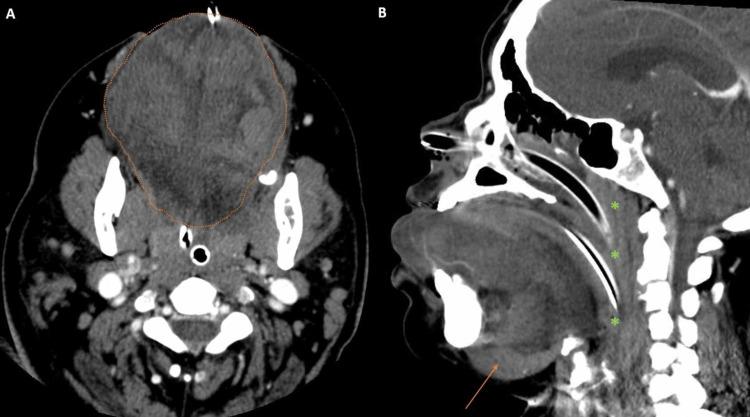

Angiotensin-converting enzyme inhibitors (ACE-i) are commonly used medications to treat hypertension and congestive heart failure. Angioedema is a well-established side effect of ACE-i and most commonly manifests as swelling of the mucosal and extra-mucosal soft tissues in the head and neck. CT with contrast is generally used to evaluate for airway compromise and to exclude other etiologies of edema. Herein we present five cases that illustrate the radiological findings specific to ACE-i-induced angioedema on enhanced CT scans.

血管紧张素转换酶抑制剂(ACE-i)是治疗高血压和充血性心力衰竭的常用药物。血管性水肿是ACE-i公认的副作用,最常见的表现为头颈部黏膜和黏膜外软组织肿胀。增强CT通常用于评估气道是否受阻,并排除其他水肿病因。在此,我们展示5例病例,以说明增强CT扫描中ACE-i诱导的血管性水肿的特异性影像学表现。